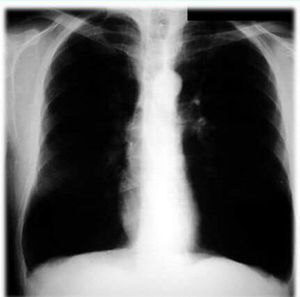

Is it emphysema

Emphysema